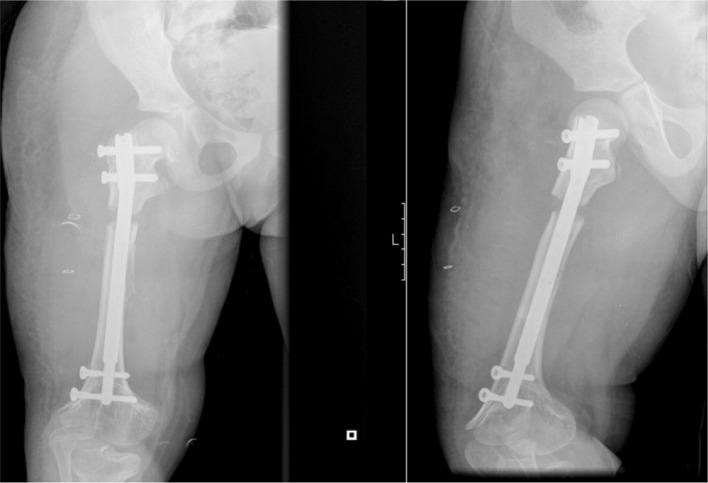

The authors present a case in which the limb lengthening has been performed in consecutive lengthening periods using the same nail. The nail was extended and retracted by altering the settings on the external remote control as well as accurately setting the rate of distraction.

After two consecutive femoral lengthening with the same PRECICE nail, the patient no longer has a significant lower limb length discrepancy and patient satisfaction was high. During this clinical case, we were not confronted with any type of complications.

作者呈现了一个病例,其中使用同一根钉子在连续的延长阶段进行肢体延长。通过改变外部遥控器的设置以及精确设定牵张速率来使钉子延长和回缩。

使用同一根PRECICE钉子连续两次进行股骨延长后,患者双下肢长度差异不再显著,患者满意度较高。在这个临床病例过程中,我们未遇到任何类型的并发症。